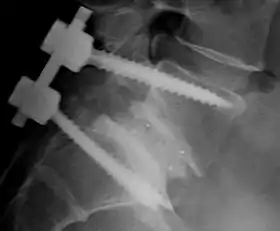

Spinal fusion, also called spondylodesis or spondylosyndesis, is a neurosurgical or orthopedic surgical technique that joins two or more vertebrae. This procedure can be performed at any level in the spine (cervical, thoracic, lumbar, or sacral) and prevents any movement between the fused vertebrae. There are many types of spinal fusion and each technique involves using bone grafting—either from the patient (autograft), donor (allograft), or artificial bone substitutes—to help the bones heal together.[1] Additional hardware (screws, plates, or cages) is often used to hold the bones in place while the graft fuses the two vertebrae together. The placement of hardware can be guided by fluoroscopy, navigation systems, or robotics.

There are many types of spinal fusion techniques. Each technique varies depending on the level of the spine and the location of the compressed spinal cord/nerves.[3] After the spine is decompressed, bone graft or artificial bone substitute is packed between the vertebrae to help them heal together.[1] In general, fusions are done either on the anterior (stomach), posterior (back), or both sides of the spine.[3] Today, most fusions are supplemented with hardware (screws, plates, rods) because they have been shown to have higher union rates than non-instrumented fusions.[3] Minimally invasive techniques are also becoming more popular.[12] These techniques use advanced image guidance systems to insert rods/screws into the spine through smaller incisions, allowing for less muscle damage, blood loss, infections, pain, and length of stay in the hospital.[12] The following list gives examples of common types of fusion techniques performed at each level of the spine:

- Posterolateral fusion is a bone graft between the transverse processes in the back of the spine. These vertebrae are then fixed in place with screws or wire through the pedicles of each vertebra, attaching to a metal rod on each side of the vertebrae.